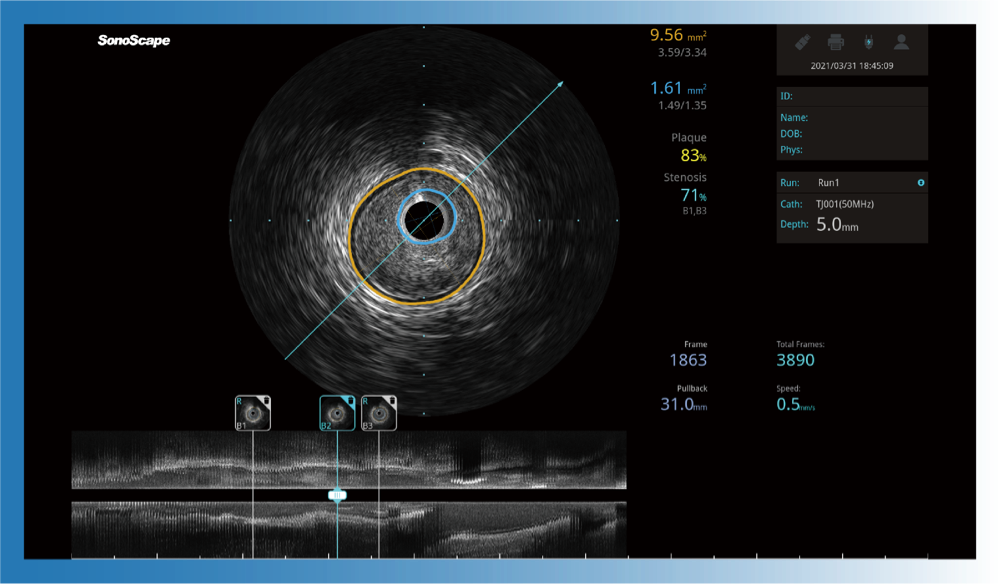

对比传统IVUS导管成像,诸侯快讯官网宽频IVUS图像的近场支架梁显影更细腻,远场中膜外血管仍清晰可辨,兼顾远中近,兼顾分辨力与穿透深度

治疗前后两次测量录像对比

简化疗效评估

一键智能描迹,自动测量斑块负荷、面积狭窄率等指标,准确率高于90%